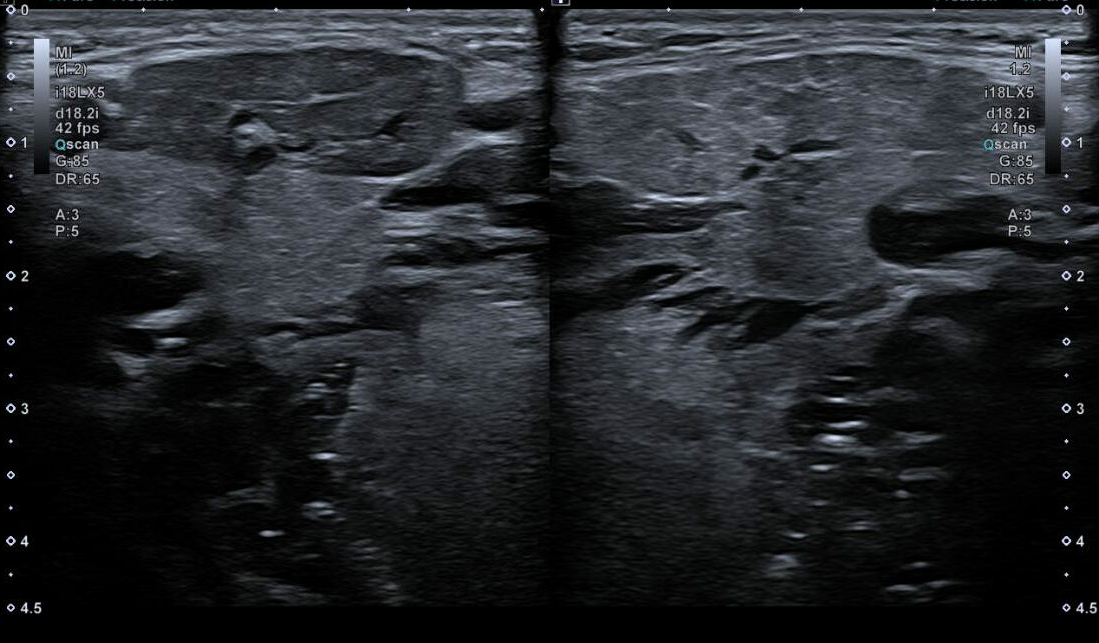

Exploración física: Tumoración dura, mal delimitada, de aproximadamente 2,5-3 cm de diámetro, adherida a planos profundos, no dolorosa. Sin signos inflamatorios cutáneos ni otras adenopatías palpables. Se realiza ecografía en consulta.

Hallazgos ecográficos

Ecografía clínica: masa hipoecogénica bien delimitada dependiente de la glándula submandibular derecha, sin evidencia de sialolitiasis. Dado el carácter inespecífico de la lesión, se deriva al servicio de Otorrinolaringología (ORL) para estudio.

Valorado por ORL, faringoscopia normal y solicitan ecografía cervical reglada, confirmándose alteración hipoecogénica de 8,6 × 27 × 21 mm en la porción superficial de la glándula submandibular derecha, globulosa, heterogénea, con bordes definidos y sin adenopatías asociadas. Dilatación ductal asociada. Se realiza PAAF ecoguiada, planteando dudas diagnósticas entre cambios inflamatorios crónicos o proceso infiltrativo.